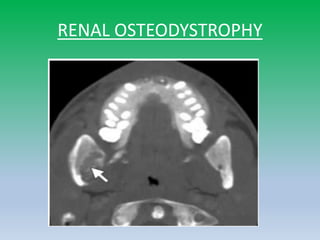

RENAL OSTEODYSTROPHY

• Loss of cortex and Lamina dura

• Loss ofcortex and Lamina dura